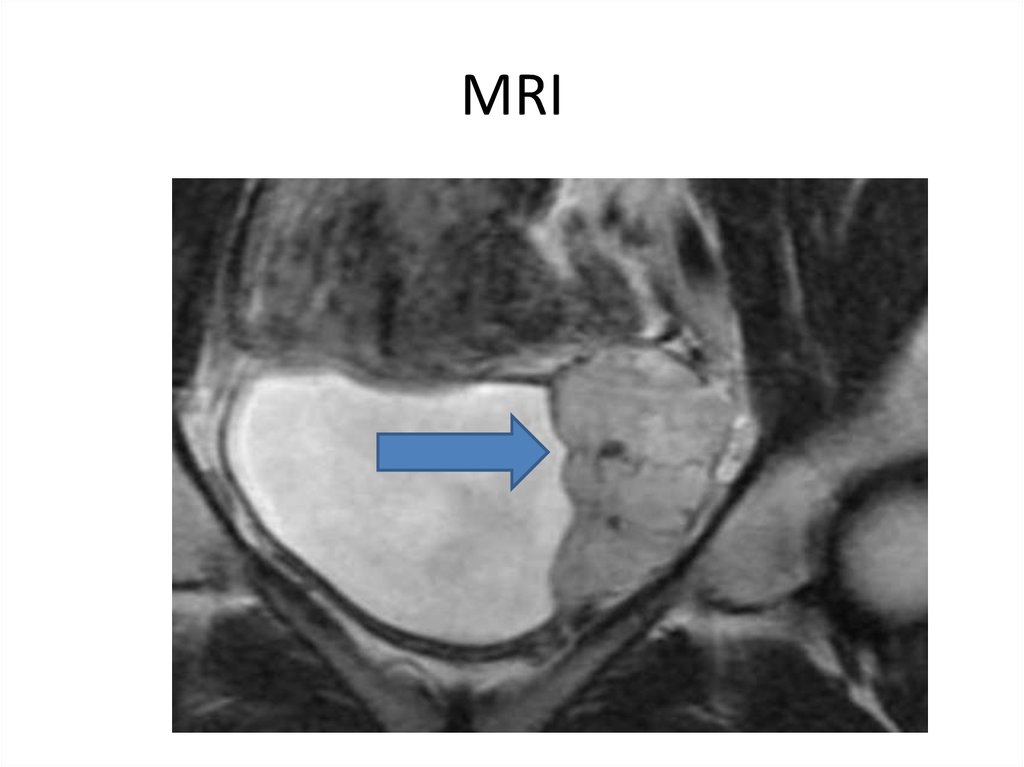

40. MRI